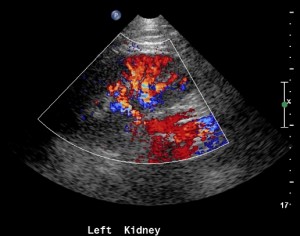

Adding color flow to this view will give a rough estimate of blood flow to the kidney. Before doing so make sure your color scale is set to low flow.